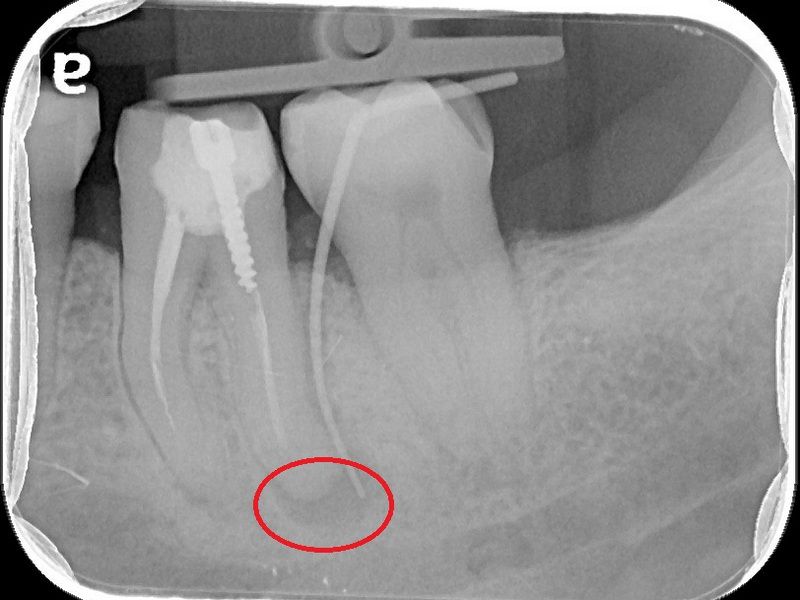

74歲的陳爺爺左下顎第一大臼齒處多年前曾接受根管治療,並裝上牙套,去年年中因為該處長了膿包,出現不適感,在坊間診所拆除舊牙套後,轉診來到台北慈濟醫院牙科部牙髓病科黃耀民醫師門診,希望在不拔牙的情況下解決膿包問題。透過X光及臨床檢查,黃耀民醫師發現膿包位在大臼齒頰側靠後方位置,且牙根底部有黑影表示有發炎狀況,左側根管內亦留存上次根管治療的分離器械。黃耀民醫師在顯微鏡視野下,利用超音波器械將根管內原有的馬來膠針封填物及分離器械移除,並徹底清潔根管系統,最後做緊密的封填。半年後回診,陳爺爺無任何不適,牙根尖的發炎狀況已經消失,膿包也未再出現,便返回原診所重做牙套。

根管治療是將根管系統做徹底的清創,藉由治療器械及殺菌藥水移除所有的牙髓組織及感染原,最後再用根管封填材料做緻密的充填,以維持清潔環境並減少病菌再次入侵感染的機會。黃耀民醫師提到,根管治療是為了增加保留牙齒的機會避免被拔除,但因為操作範圍狹小,且根管型態複雜多變,且可能還有根管彎曲、鈣化阻塞等現象,過去只能倚靠醫師臨床經驗及手感進行治療,容易有清創程度不足而導致治療效果不佳的現象。而牙科顯微鏡是現今輔助治療的新趨勢,可提供充分的照明及最大25至30的放大倍率,讓醫師更能看清楚根管系統,再搭配超音波器械,以最少破壞齒質的方式,做最大程度的清潔。一般而言,傳統根管治療的成功率約7至8成,而顯微鏡輔助根管治療的成功率可高達9成。

牙科顯微鏡除了適用於複雜型根管系統的治療外,在根管穿孔修補、根管內分離器械移除、齒裂檢查、活髓治療等方面都扮演重要的角色。另外,在根尖手術或牙周病手術時若能搭配顯微鏡,則更能有效清除掉肉眼不易看見的發炎感染組織,提高治療的成功率。牙周病科蘇穎珊醫師也表示牙科顯微鏡也是牙周治療的新利器,除了可以精細觀察牙周病灶以及精確找到致病因子進行有效的清潔,在手術治療上藉由放大設備可以進行微創治療減小傷口,縮短癒合期,提高治療的效率。